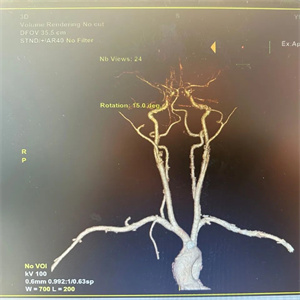

小李同学(化名),13岁在放学途中不慎摔倒,手中的香肠签子意外自左侧口角插入口腔内,“口腔异物半小时”急诊入住我院口腔科。入院后,经过紧急颌面颈部CT及CTA等一系列检查,发现异物由左侧舌体斜向插入咽部,紧贴颈椎前缘到达右侧颈动脉深面,且异物距离颈动脉仅有3mm,情况十分危急。